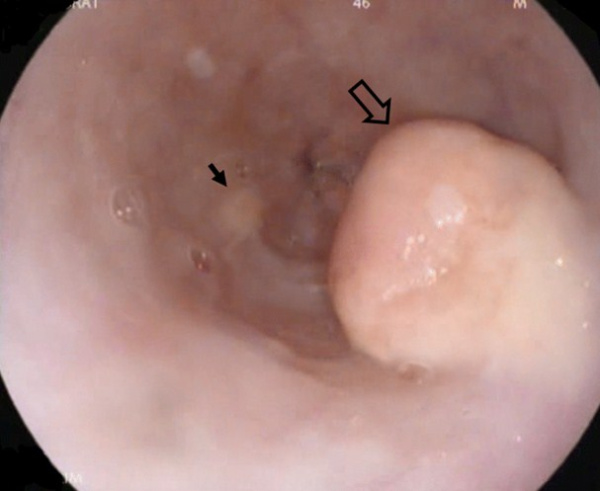

(Слева) На аксиальной КТ с контрастным усилением у пациента с разрывом опухоли червеобразного отростка визуализируются большие гиподенсные музцинозные метастазы, из-за которых края печени выглядят «фестончатыми» — типичные изменения при псевдомиксоме брюшины. В периферических отделах (как минимум одного из них определяется обызвествление).

(Справа) На корональной КТ с контрастом (объемный рендеринг) у этого же пациента можно рассмотреть весь объем распространенного поражения при псевдомиксоме; очаги окружают печень и желудок, обнаруживаются также в полости таза. (Слева) На аксиальной КТ с контрастным усилением у пациента с псевдомиксомой брюшины после разрыва опухоли аппендикса определяются множественные кистозные очаги, занимающие значительную часть объема верхних отделов брюшной полости, в некоторых очагах визуализируются тонкие кальцинаты извитой формы.